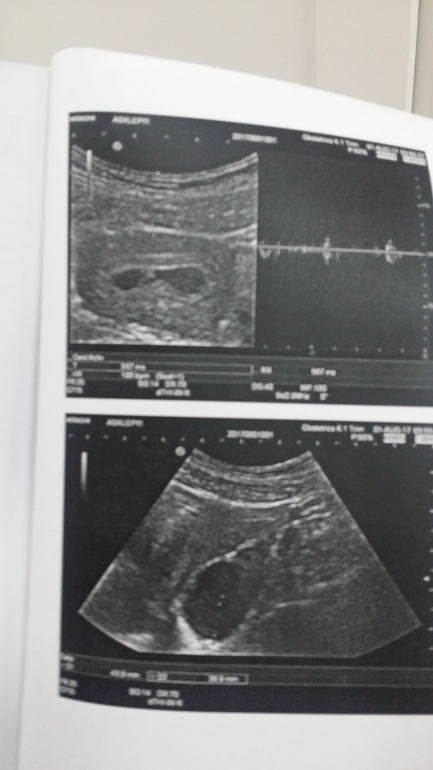

4 недели от зачатия, 6 акушерства недель, сб 106 уд/мин. Так что должны увидеть эти заветные зигзаги "кардиограммы"

В 4 недели от зачатия уже должны зарегистрировать сердцебиение. а так, конечно, эмбриончик на таком сроке очень маленький 3-6 мм

У меня цикл нерегулярный и овуляция поздняя. На узи пошла в 7 недель, по эмбриональному было 5 недель, все увидели и услышали